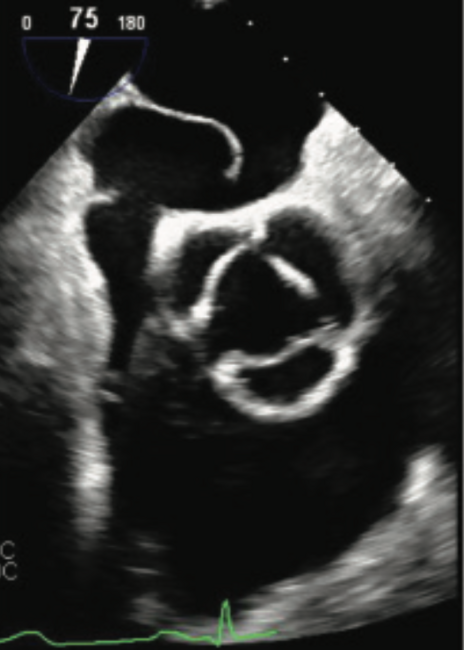

He was admitted with diagnosis of acute hypoxic respiratory failure secondary to a presumptive diagnosis of hypersensitivity pneumonitis given his history and was started on intravenous steroids. Despite treatment, he continued to get progressively hypoxemic, requiring high-flow O2. After an extensive and detailed pulmonary workup at the outside facility, he was transferred to our facility for further evaluation and management. Repeat echocardiography demonstrated a large PFO using agitated saline. A subsequent transesophageal echocardiogram (TEE) revealed normal biventricular size and function, an atrial septal aneurysm (Figure 1), and color-flow Doppler suggested the presence of a PFO with predominant right-to-left shunting (Figure 2). Right heart catheterization demonstrated normal central filling pressures with no evidence of left-to-right shunting.

Given the degree of right-to-left shunting with agitated saline at baseline, there was a high index of suspicion for Platypnea-orthodeoxia syndrome. Repeat echocardiography with agitated saline in both supine and upright position was performed and demonstrated a profound right-to-left shunt within one cardiac cycle in the upright position (Figures 3-4).